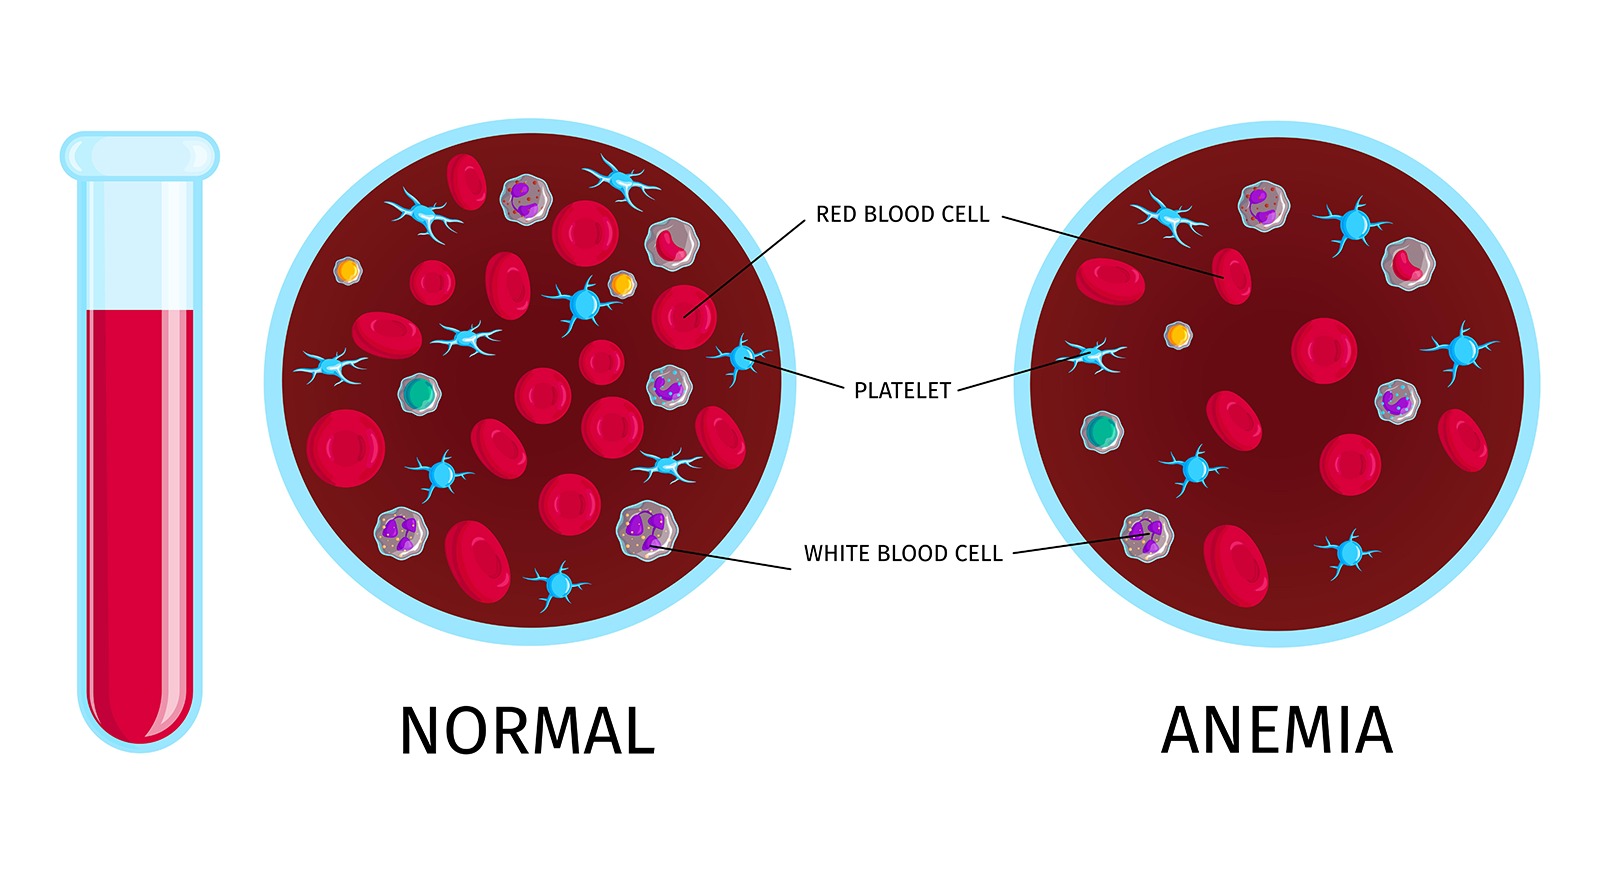

एनीमिया (खून की कमी) से बचने के आसान घरेलू उपाय

आज की भागदौड़ भरी जिंदगी में लोग अक्सर अपने खान-पान और स्वास्थ्य पर ध्यान नहीं दे पाते। इसका सबसे आम असर खून की कमी यानी एनीमिया (Anemia) के रूप में सामने आता है। एनीमिया एक ऐसी स्थिति है, जब खून

एनीमिया (खून की कमी) से

आज की भागदौड़ भरी जिंदगी में लोग अक्सर अपने खान-पान और स्वास्थ्य पर ध्यान नहीं दे पाते। इसका सबसे आम असर खून की कमी यानी एनीमिया (Anemia) के रूप में...